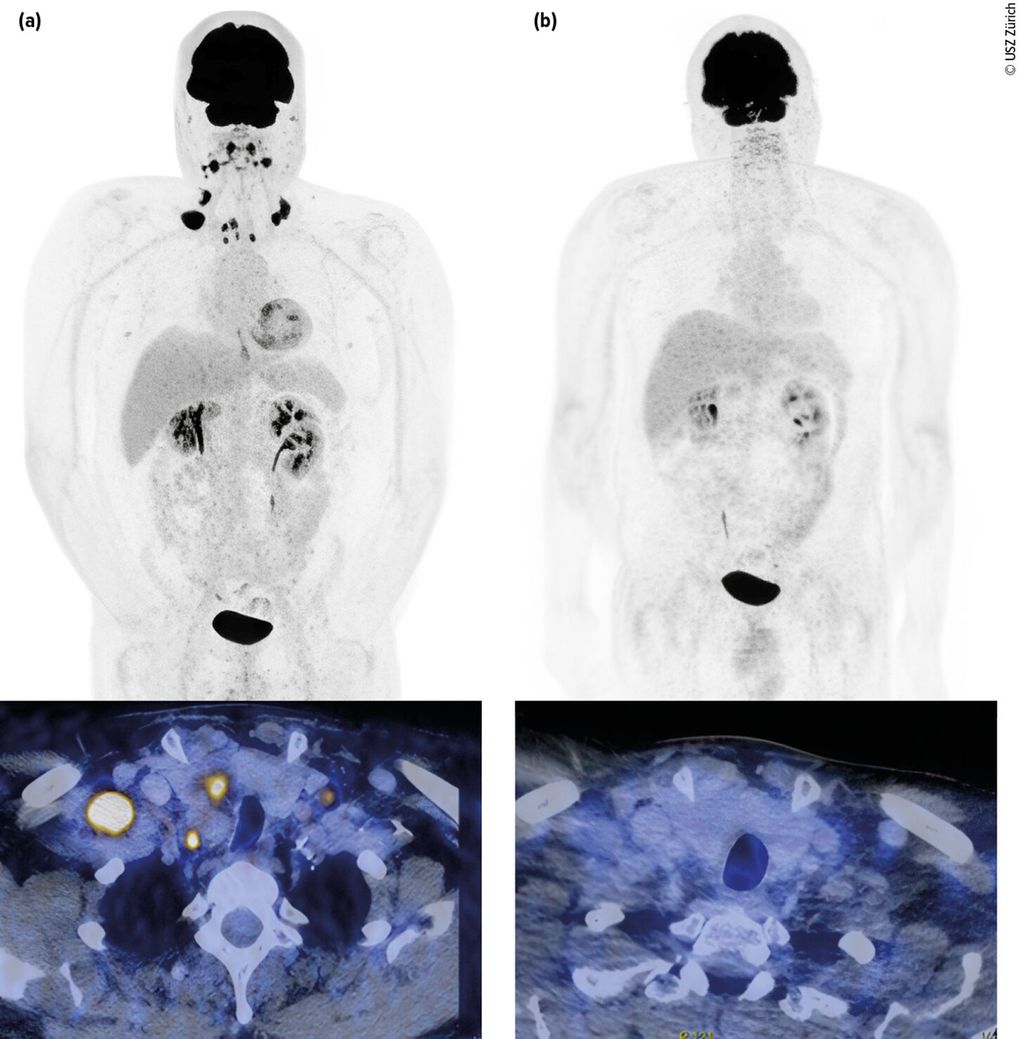

Abb. 1: Urothelkarzinom der Harnblase (initial cT3 cN3 cM0) mit metachron aufgetretener lymphogener Metastasierung. Staging mittels Computertomografie (PET-CT) mit Diagnose der lymphogenen Metastasierung (a, links). Erstes Restaging zwei Monate nach Therapiebeginn mit EV+P (b, rechts). Bildmorphologisch zeigt sich eine Komplettremission. Der Patient befindet sich weiterhin in anhaltender Remission. Bilder und Patient USZ Zürich

Der lokal fortgeschrittene und metastasierte Blasentumor stellt weiterhin eine therapeutische Herausforderung dar. Die Prognose ist trotz jüngster Fortschritte in der Systemtherapie weiterhin meist schlecht. Die Wahl der Erstlinienbehandlung orientiert sich seit Zulassung der Kombinationstherapie mit dem Antikörper-Wirkstoff-Konjugat (ADC) Enfortumab Vedotin (gerichtet gegen Nectin-4) in Kombination mit dem PD-1-Checkpoint-Inhibitor Pembrolizumab (EV+P) an der Tauglichkeit für diese Kombination vs. Nicht-Tauglichkeit.

Das mediane OS konnte mit dieser Kombination signifikant auf knapp 34 Monate im Vergleich zu 16 Monaten mit alleiniger platinhaltiger Chemotherapie ± IO-Erhaltung gesteigert werden. In der Studie waren auch Patient:innen mit schlechterem Allgemeinzustand (bis ECOG 2) und Patient:innen mit reduzierter Nierenfunktion (GFR ≥30ml/min) eingeschlossen. Ein Update mit einem Follow-up von nun 2,5 Jahren zeigt, dass die Patient:innen, die eine komplette Remission (CR) erzielen, auch längerfristig in einer CR bleiben.6